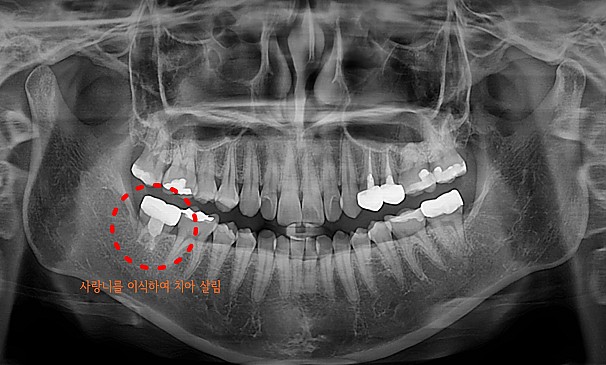

자가치아이식술란?

도저히 살릴 수 없는 치아를 뽑고 그 자리에 자신의 사랑니를 이식하는 치료방법입니다.

기능이 없는 사랑니를 이동하여 이식함으로써 내 자연치아를 사용할 수 있습니다.

모OO님 전후사진 | 치료 기간 : 2주

치료 전